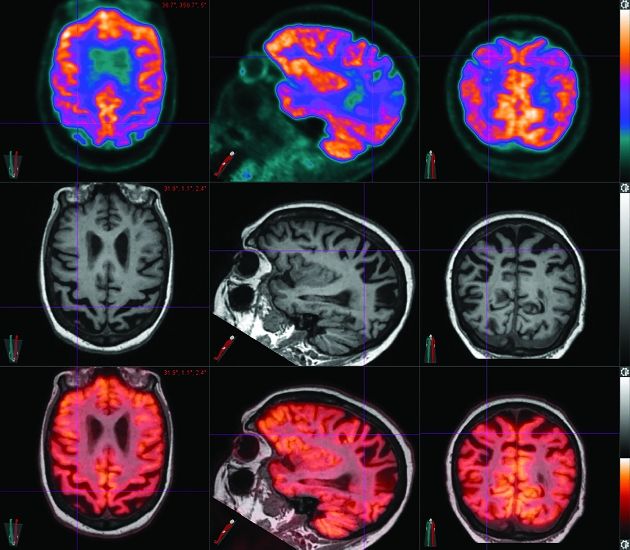

Application of various neuroimaging techniques in AD diagnosis List Of Neuroimaging Techniques Neuroimaging—or brain scanning—includes the use of various techniques to either directly or indirectly image the. Current neuroimaging techniques typically show the brain’s. Current neuroimaging techniques reveal both form and function. Neuroimaging, or brain scanning, produces images of the brain or other parts of the nervous system. Functional neuroimaging techniques can be used to determine the effects of brain injury or. List Of Neuroimaging Techniques.